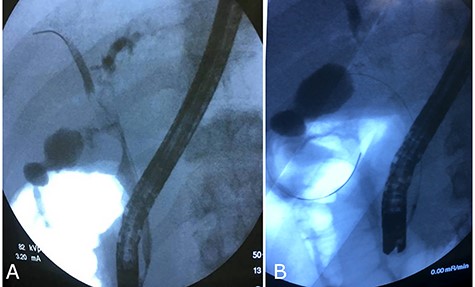

The patient and his parents disagreed to perform firstly a computered tomography scan, and then an magnetic resonance cholangiopancreatography. Unusually, they agreed about endoscopic retrograde cholangiopancreatography (ERCP), so it was performed and cholangiography showed an ab-extrinsic stricture of CBD caused by a compression from a biliary stone in the infundibulum of the gallbladder; the upper biliary duct was dilated with various defects as biliary sludge and stones (Fig. 1A). Moreover, late opacification of gallbladder showed lithiasis and, more important, an unexpected opacification of the right colonic lumen (Fig. 1B). MS with both cholecystobiliary (due to the erosion of the wall of the CBD that involves up to two-thirds of its circumference) and cholecystocolonic fistula without gallstone ileum was diagnosed and classified as type III according to Csendes et al. [4] and type V according to Beltran et al. [5]. A partial toilette of CBD was undergone, arranging a drainage with a biliary ‘pigtail’ prob, but the surgical treatment was immediately undergone due to the evidence of fluid faecaloid-like aspiration through the biliary drainage.

Cholangiography first ERCP. (A) Ab extrinsic compression of CBD; (B) tardive opacization of gallbladder showing fistula with colon.